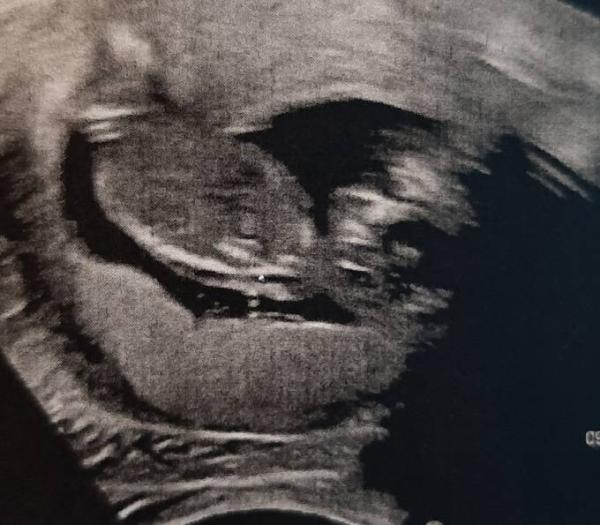

Hallo ihr lieben, wir kommen gerade aus dem Krankenhaus, mein Sohn ist heute auf meinen Bauch gefallen und ich hab seit 13 Uhr Schmerzen, erst dumpf, dann stechend. Sind also hin, auch aufgrund der Vorderwandplazenta. Es ist aber alles super, Babymaus Turnt fleißig. Soll mich jetzt schonen mit dem Bauchtrauma. Ich hoffe euch geht es gut

Bild zu Stumpfes Bauchtrauma - Forum für April - Mamis